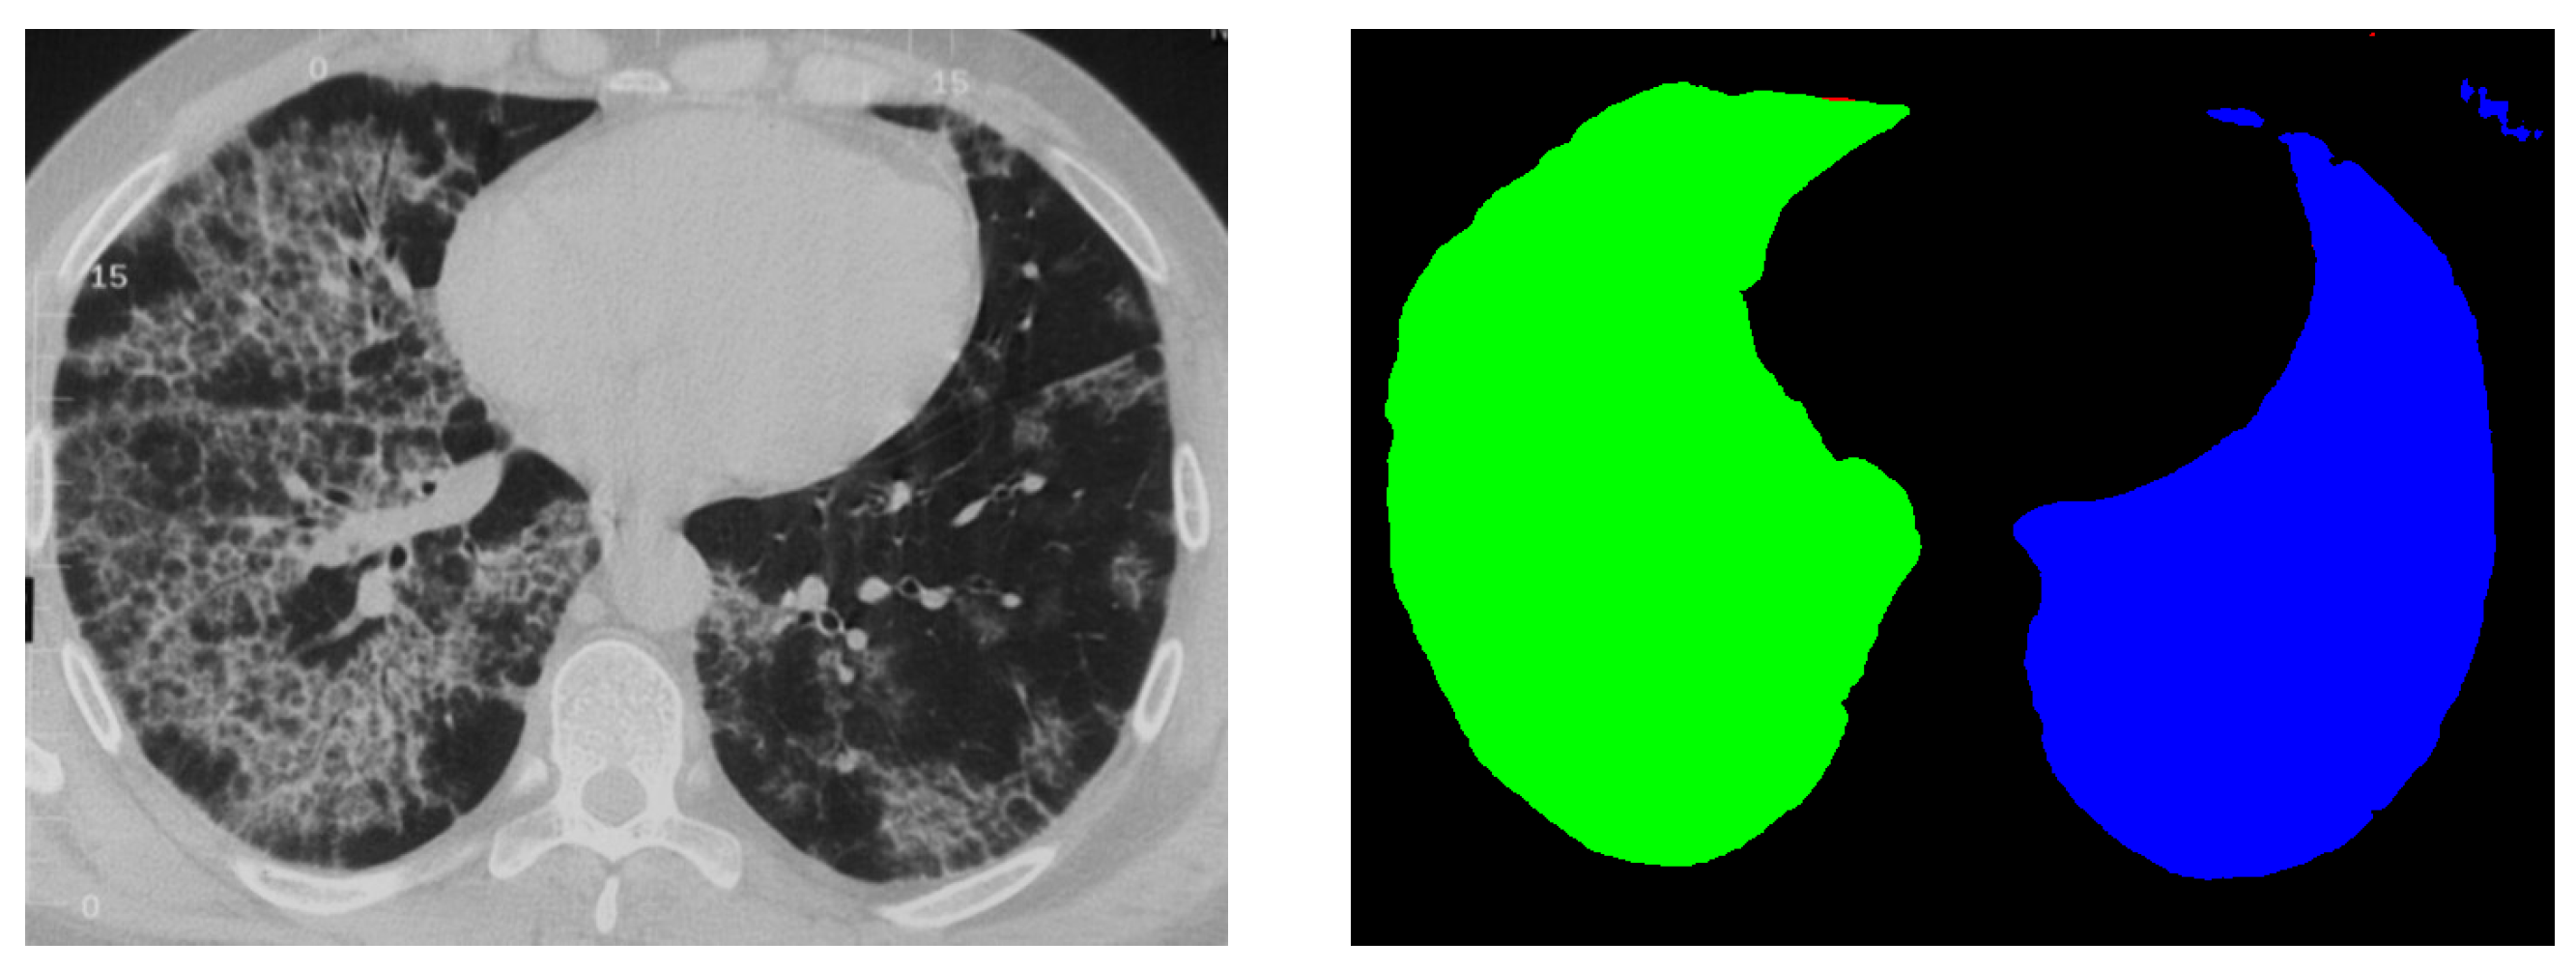

4.2. Qualitative Results